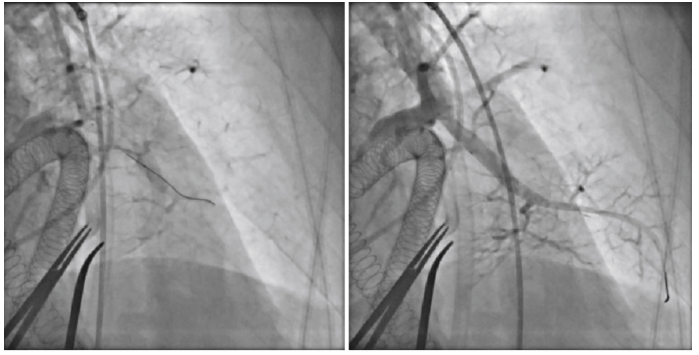

Procedure's name - findings - indications

Pulmonary Balloon Angioplasty - may be done for inoperable CTEPH